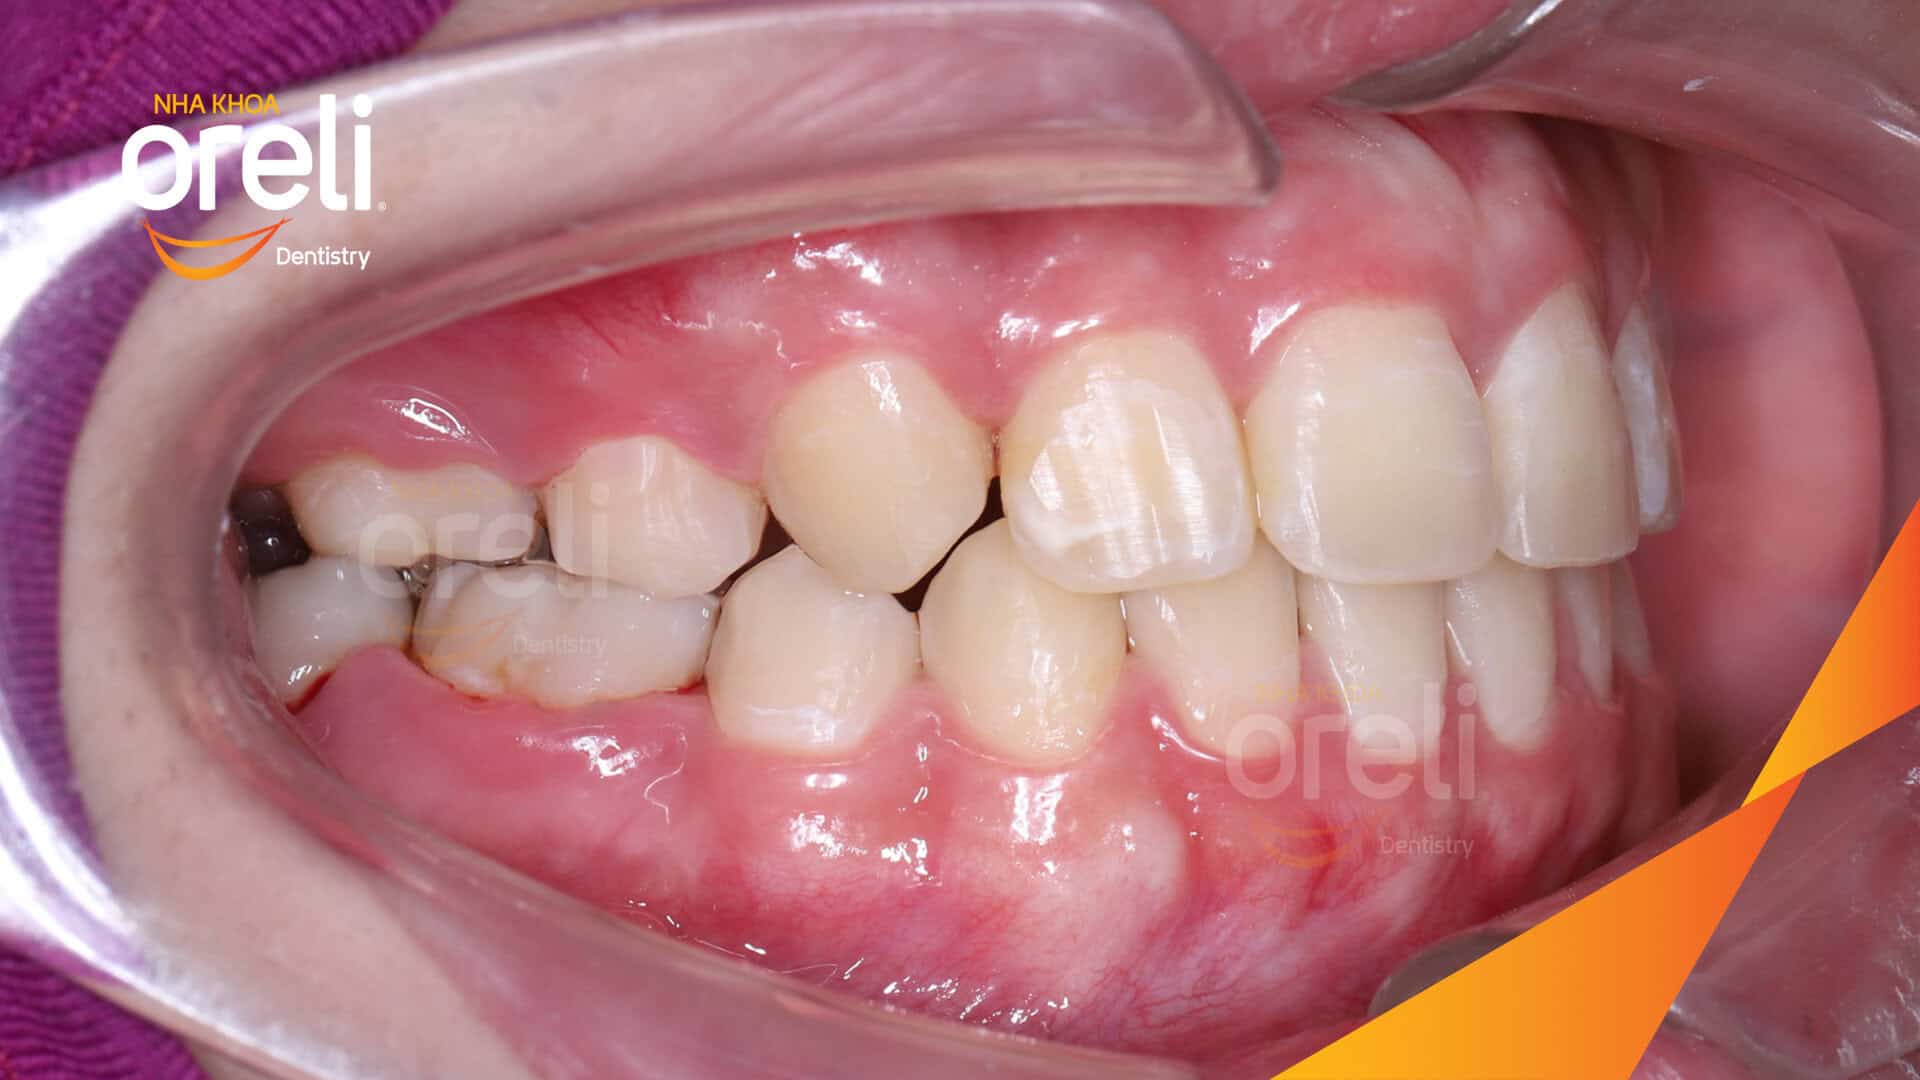

Tình trạng: Nhô xương ổ, trục răng nghiêng trước hai hàm, độ nhô môi nhiều

Giải pháp: Nhổ răng 4 chỉnh hô

Thời gian: 24 tháng

Kết quả: Nụ cười hài hòa, mặt nghiêng đẹp, trục răng cửa đứng